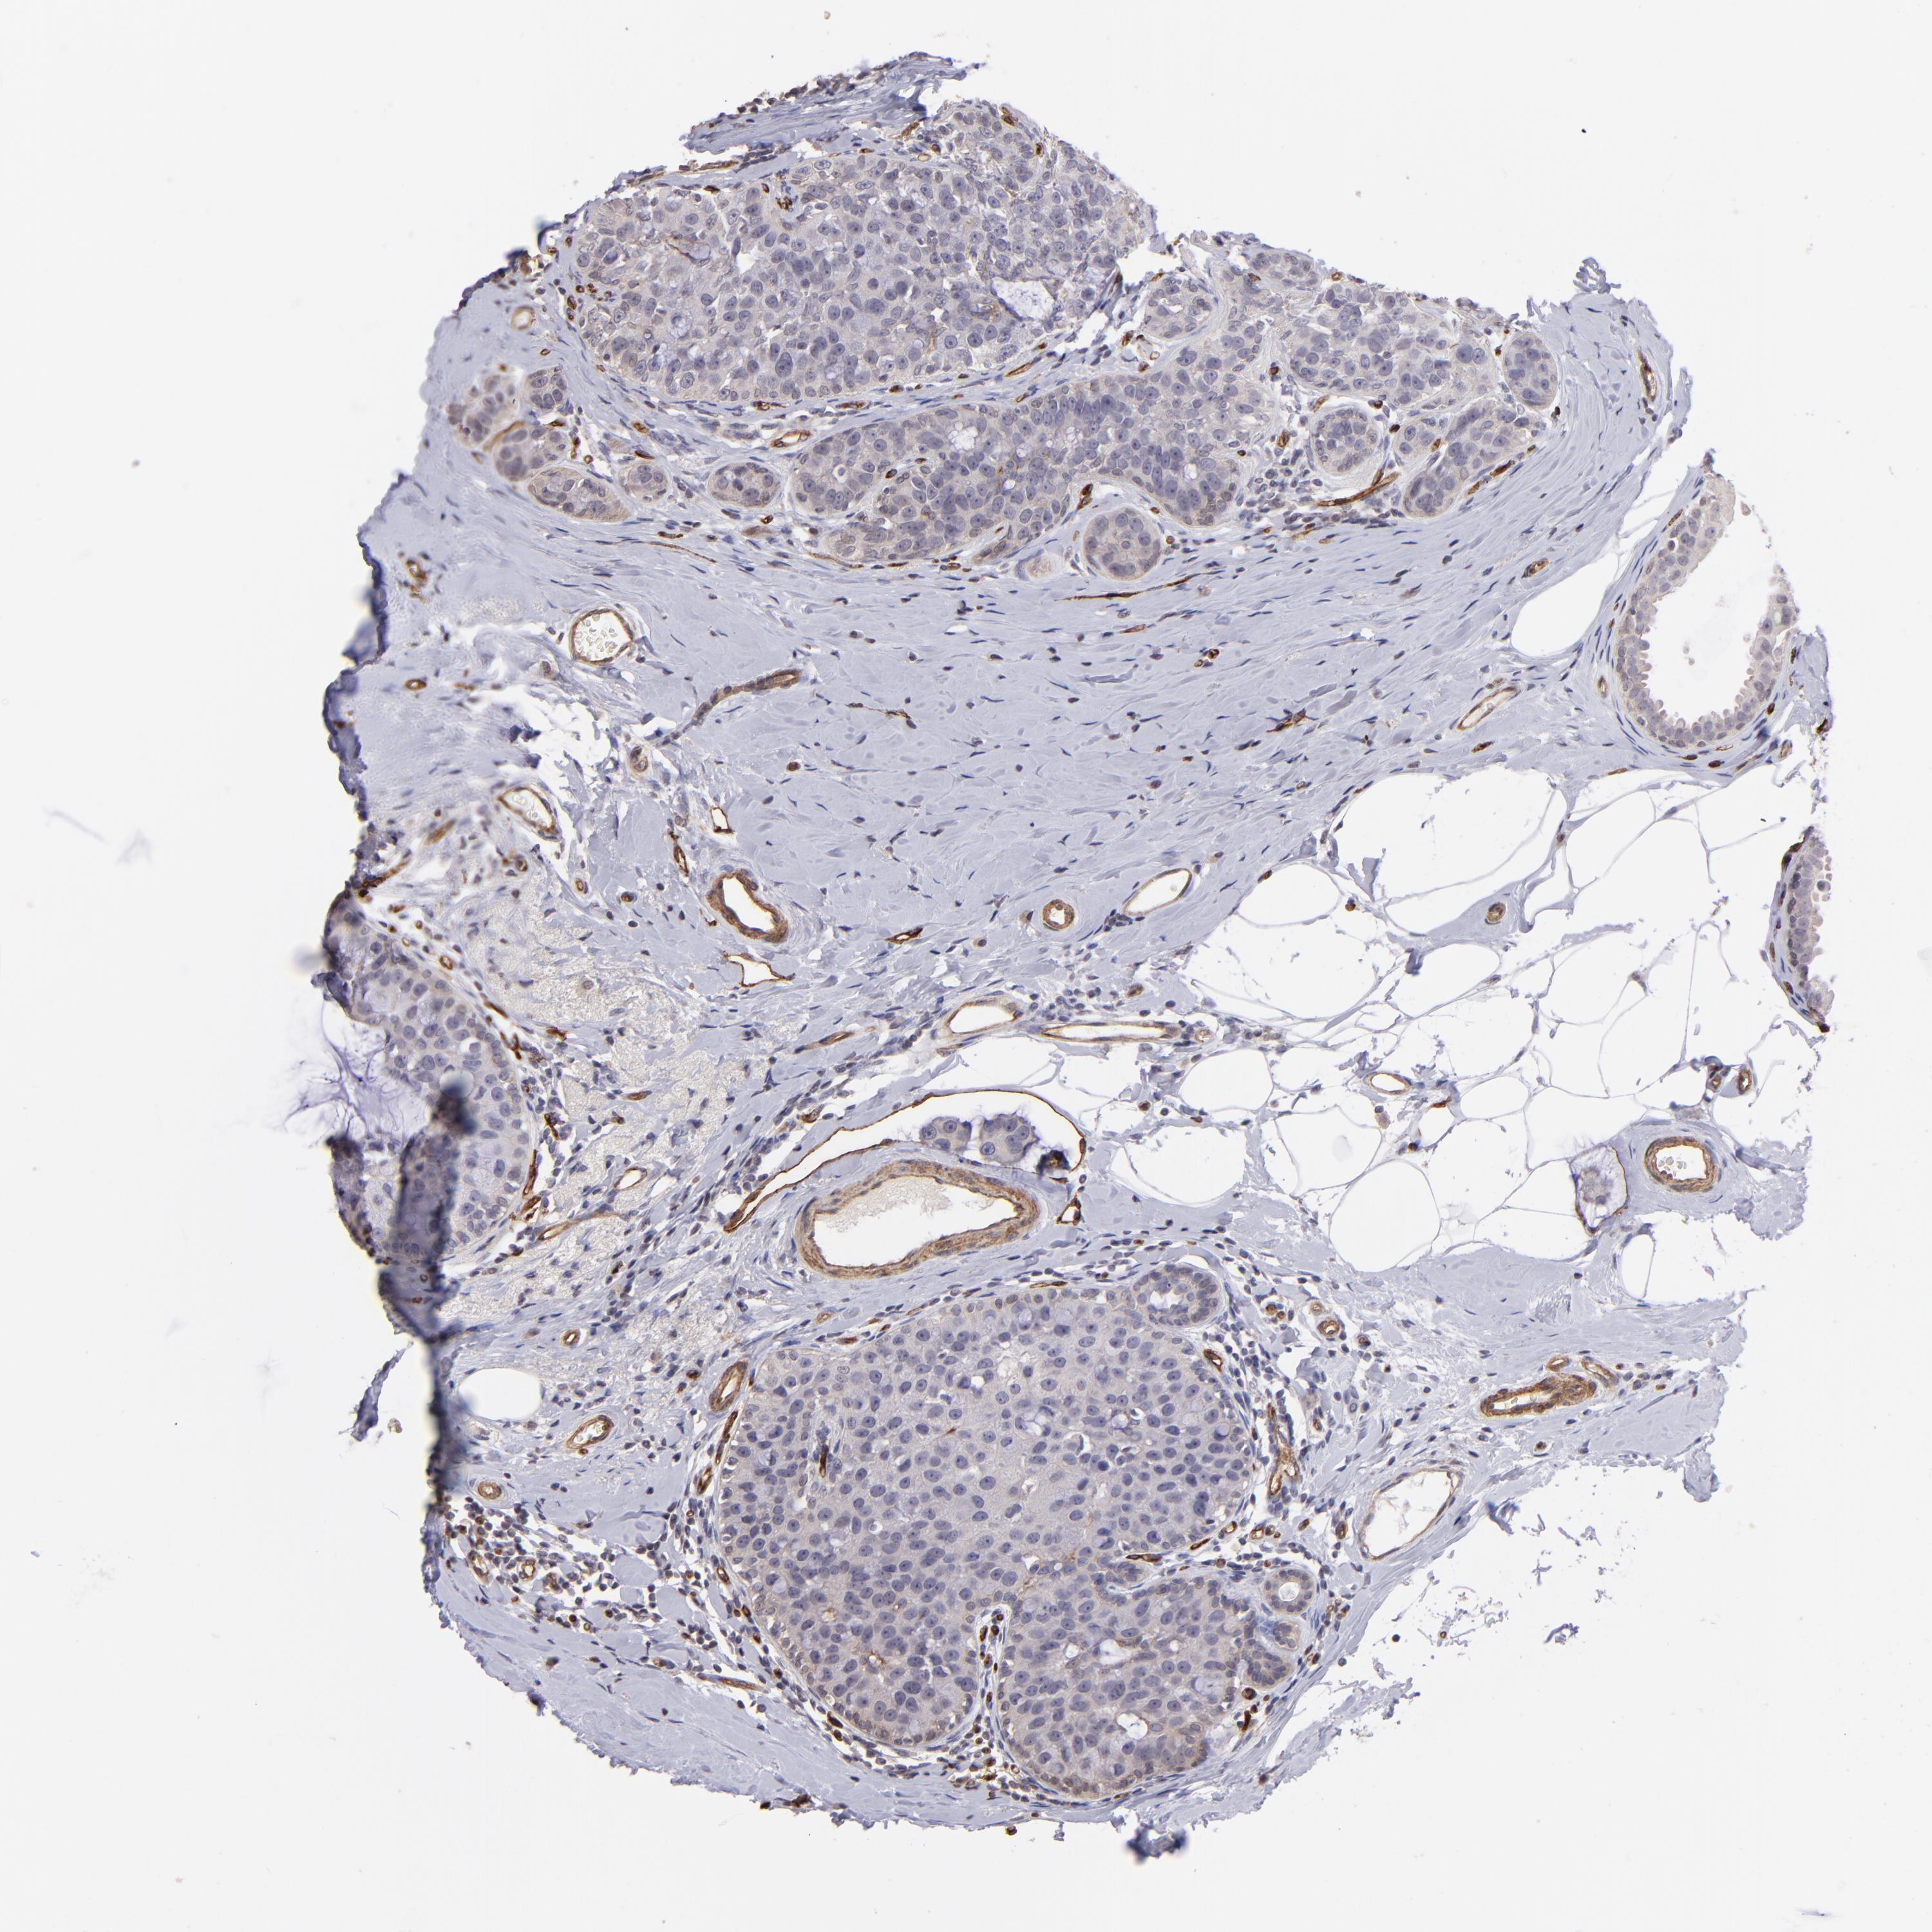

BRCA TCGA BRCA VALIDATION PROTEIN EXPRESSION